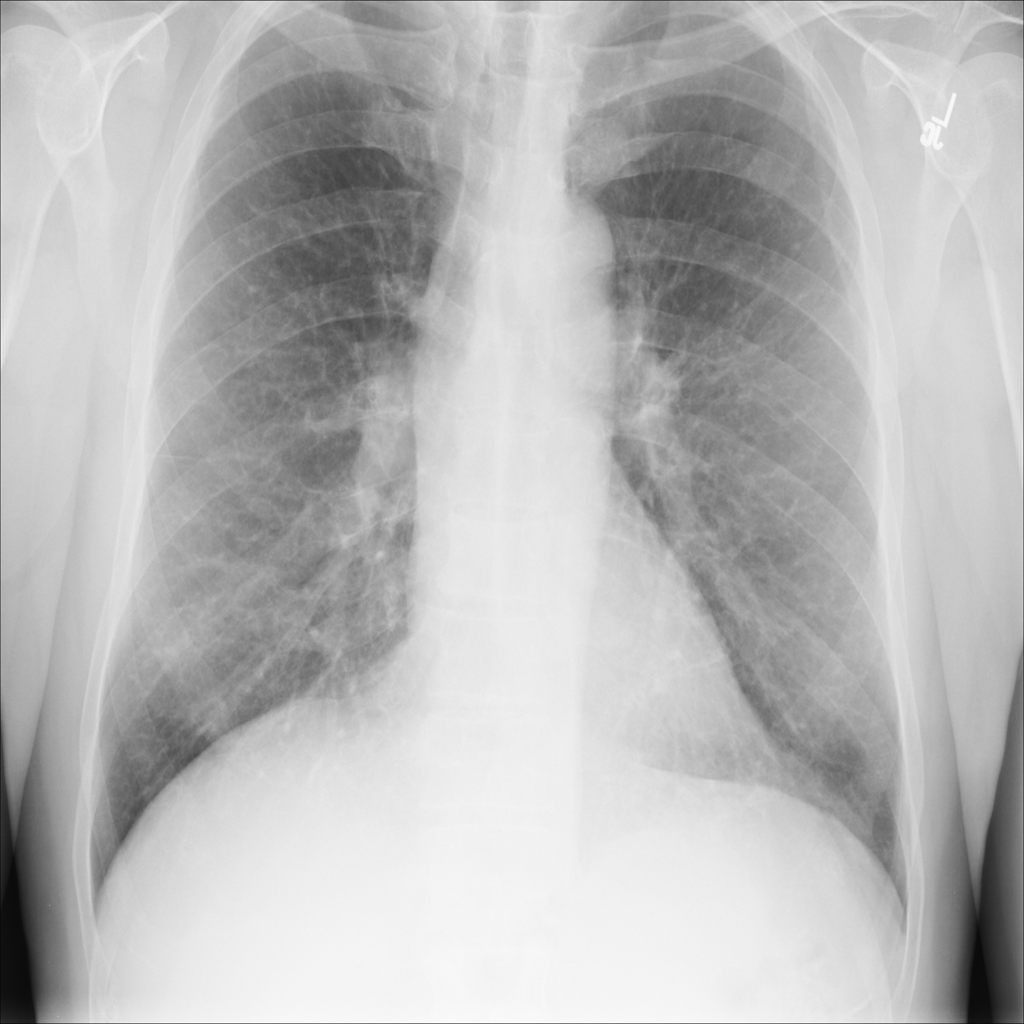

PAT-E960 · IMG-002Fibrosis

PAT-E960 · IMG-002

PA